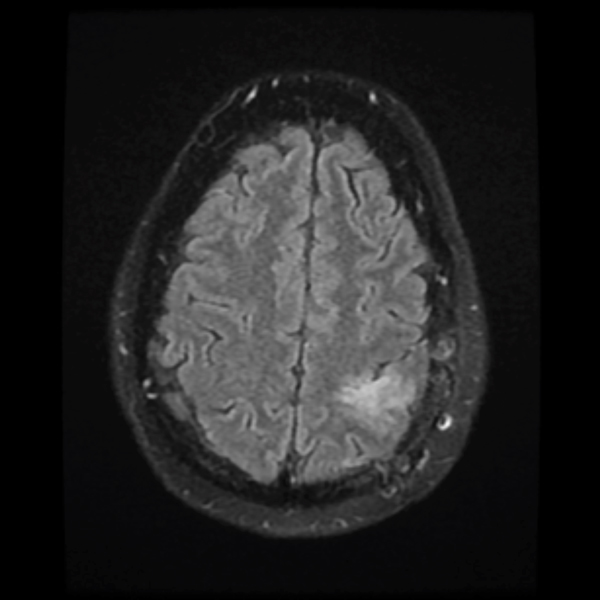

Treatment with chemotherapy and radiation under the care of Dr. Grewal resulted in a durable response of the tumor as evident in the post-treatment images.

July 2019